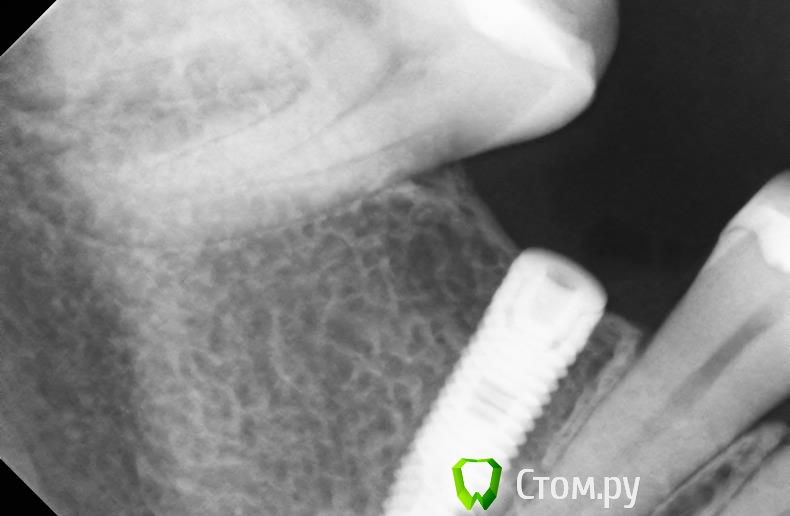

bullbull Опубликовано 15 апреля, 2014 Поделиться Опубликовано 15 апреля, 2014 Здесь используется имплантиум - резьба двойная. Иногда, когда недостаточно прошли контрсинком во время установки кость как бы "бледнеет" вокруг импланта, особенно если торк больше 50-60. В таких случаях наблюдается воронковидная резорбция немногим ниже второй резьбы. Глубже может и не распространяться. При перегреве (использовании старой фрезы, прошедшей более 100 погружений; высокой скорости; недостаточного охлаждения) больше страдает плотная кость, где-то до 50% от длины импланта, глубже, обычно, нагрев меньше.Это только моё мнение, основанной на паре-тройке сотен установленных коллегами и мной корейских винтах. Ссылка на комментарий

Opimar Опубликовано 18 апреля, 2014 Автор Поделиться Опубликовано 18 апреля, 2014 Вчера удалил. Имплантант держался за язычную стенку. Тонким бором подпилил и вывихнул элеватором. Откюретажил. 2 кисты и 4х стеночный дефект. Сохранилась по большей части чзычная стенка, хотя и от вестибулярной кое что осталось. Теперь через 8 недель сделаем кт . Ссылка на комментарий